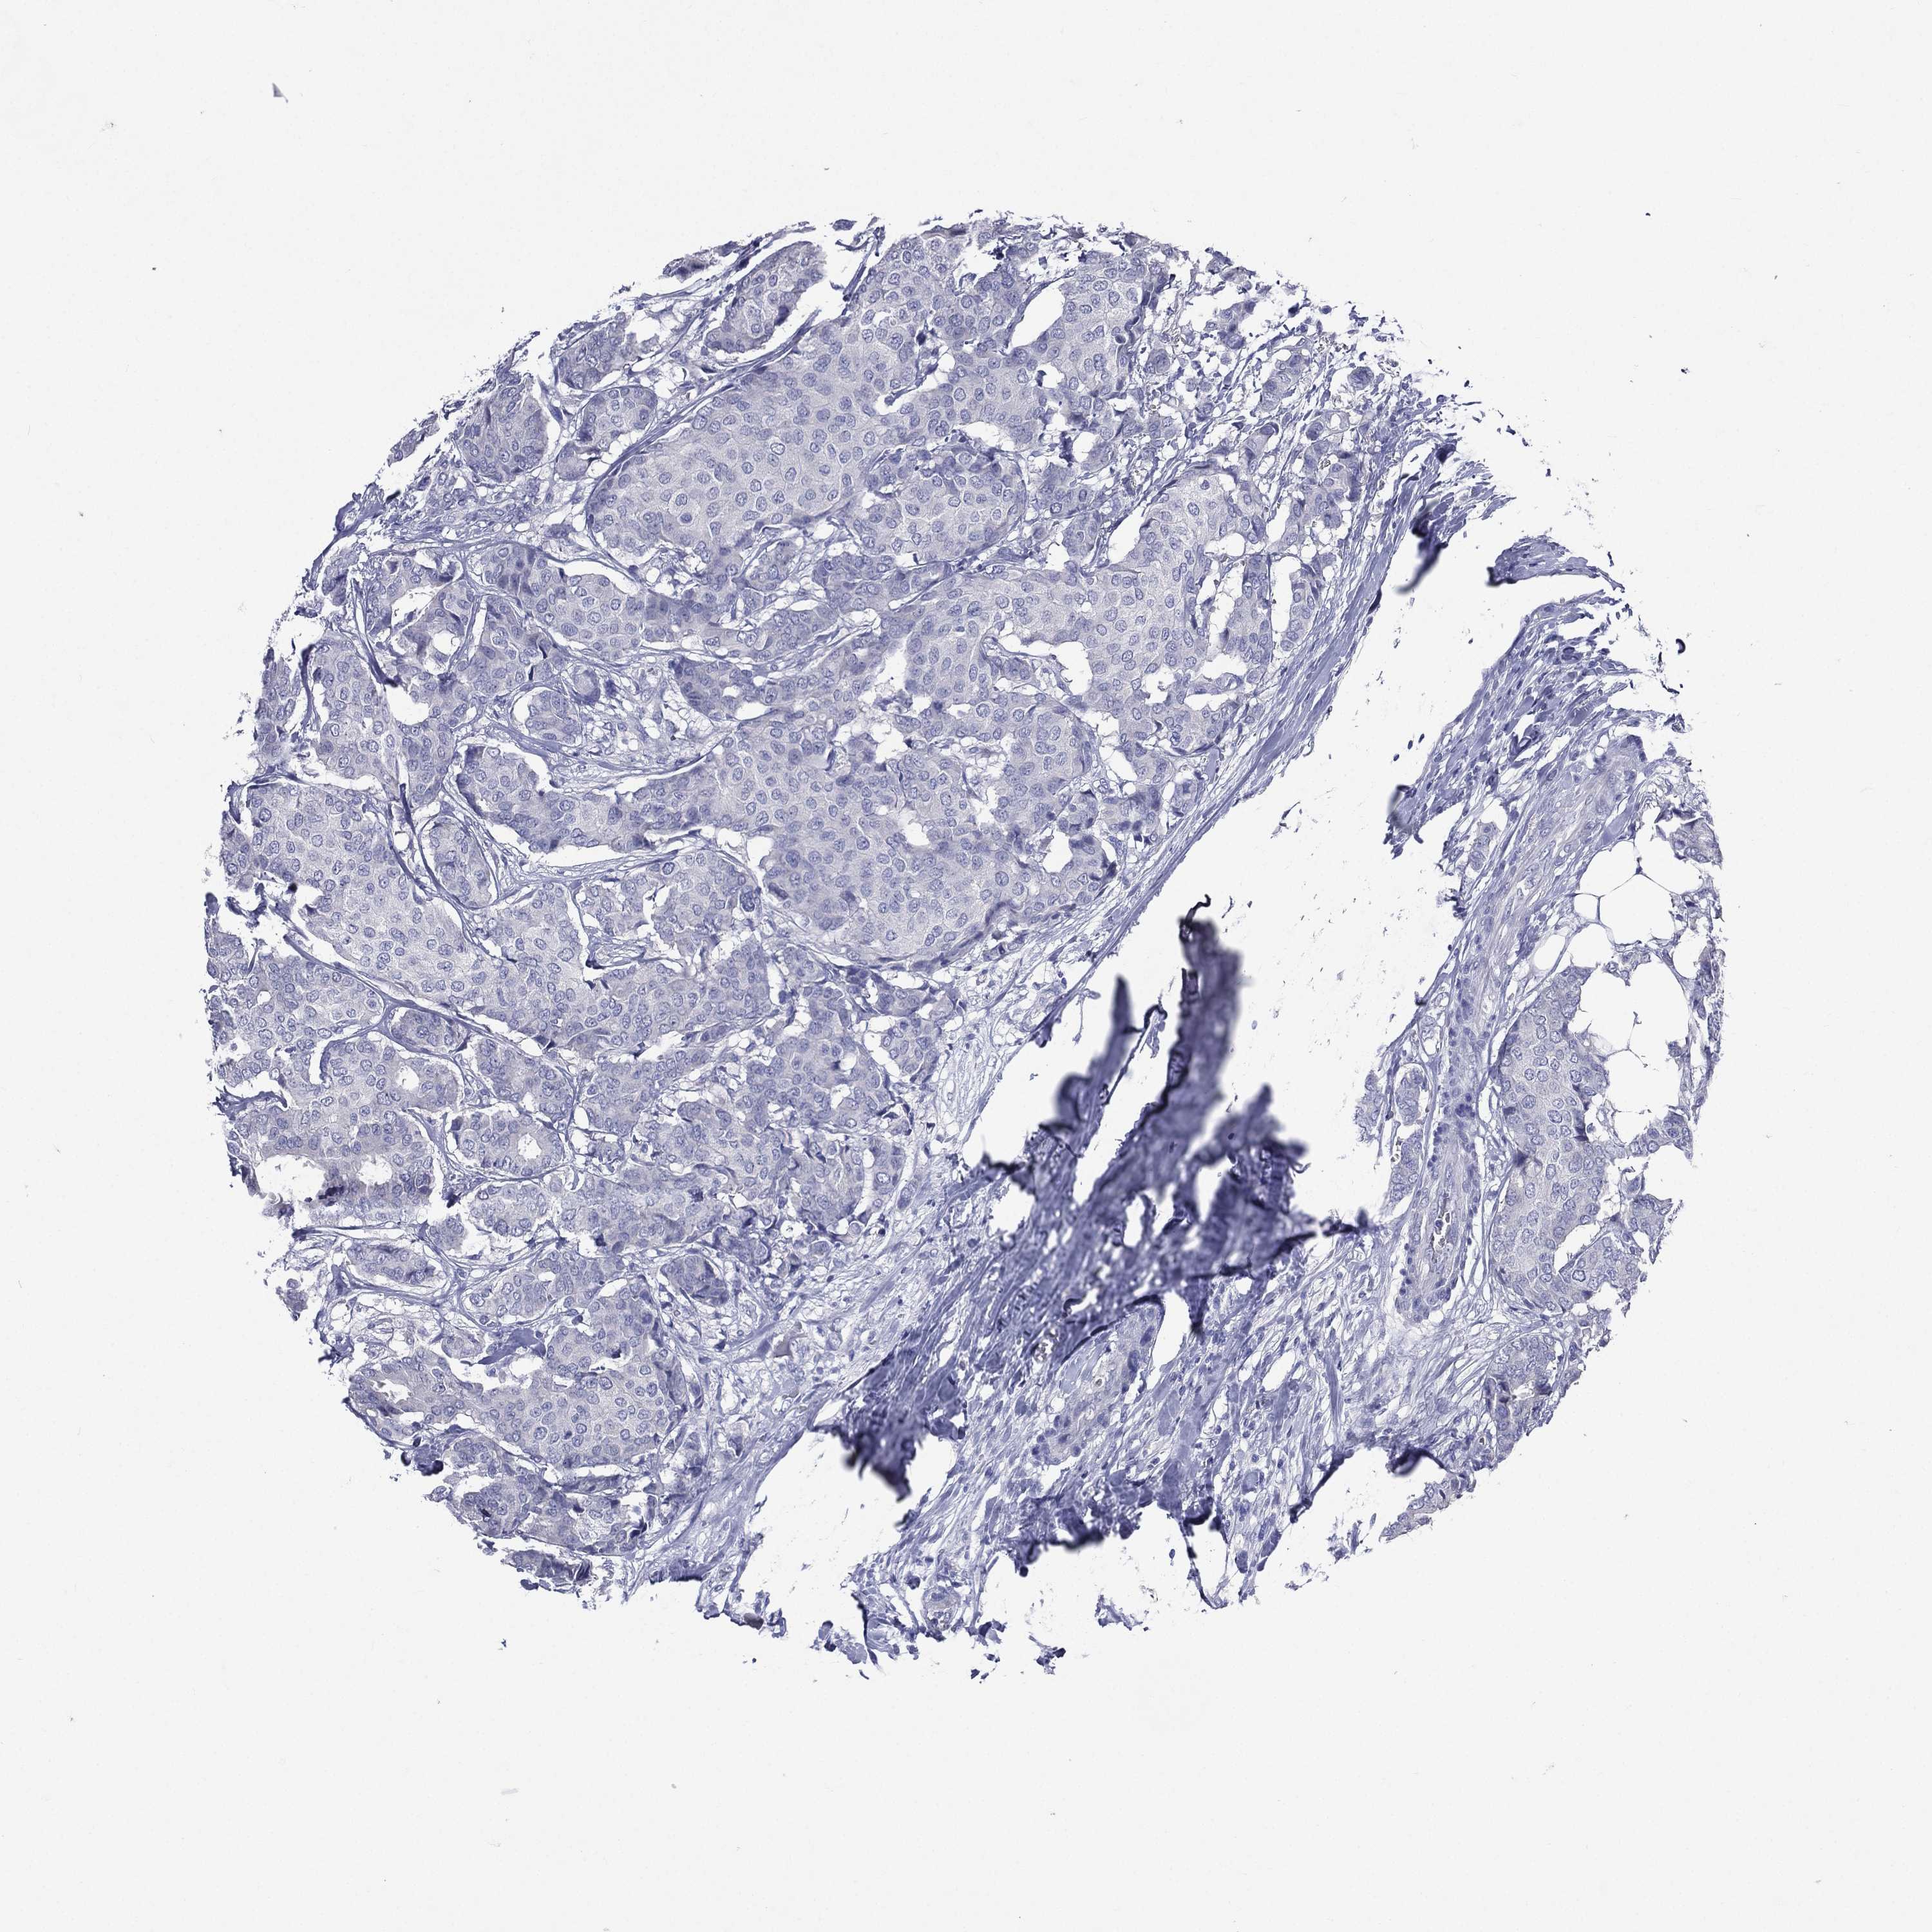

CANCER BREAST CANCER Show tissue menu

BRCA TCGA BRCA VALIDATION PROTEIN EXPRESSION